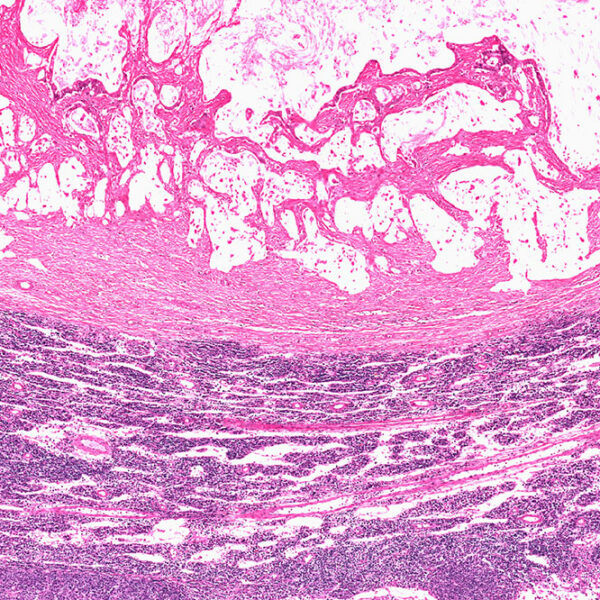

The condition, characterized by a malignant tumor, begins in the nerve cells of the digestive system. With time, they mutate and affect the normal functioning of the cells in the organ. Patients experience symptoms like anemia, abdominal pain, and vomiting, and these further aggravate if the condition is not treated. Therefore, ensure that you consult your doctor at the earliest.